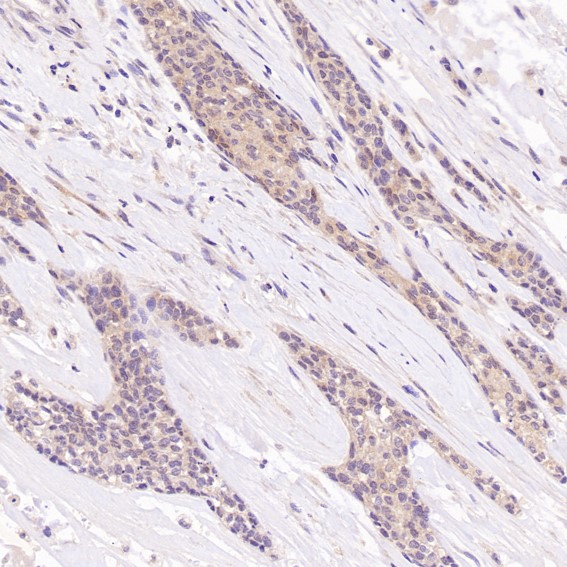

Immunohistochemical analysis of paraffin-embedded Human breast cancer, using the Antibody at 1:200 dilution.

Immunohistochemical analysis of paraffin-embedded human breast cancer, using Hsc70 Antibody.